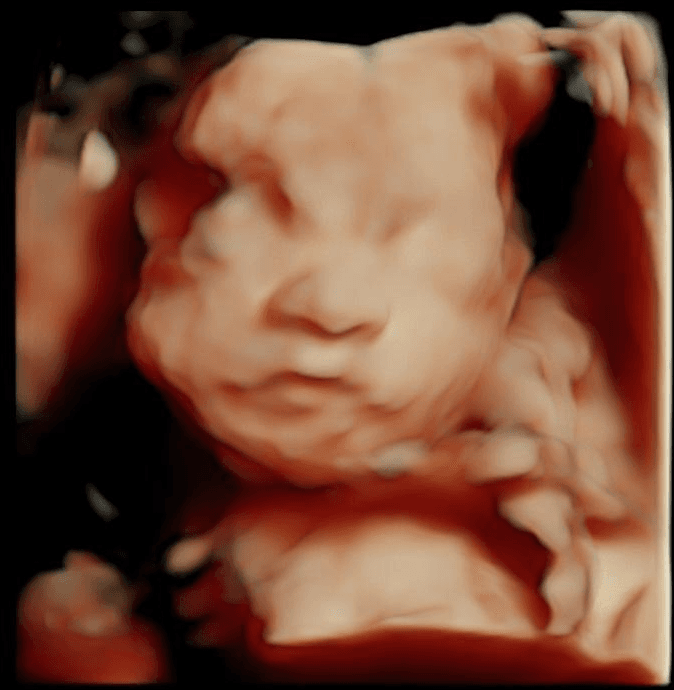

This FREE tool allows you to safely crop the image, focusing only on the ultrasound itself:

We only use your images for cropping purposes and will never share them with anyone.